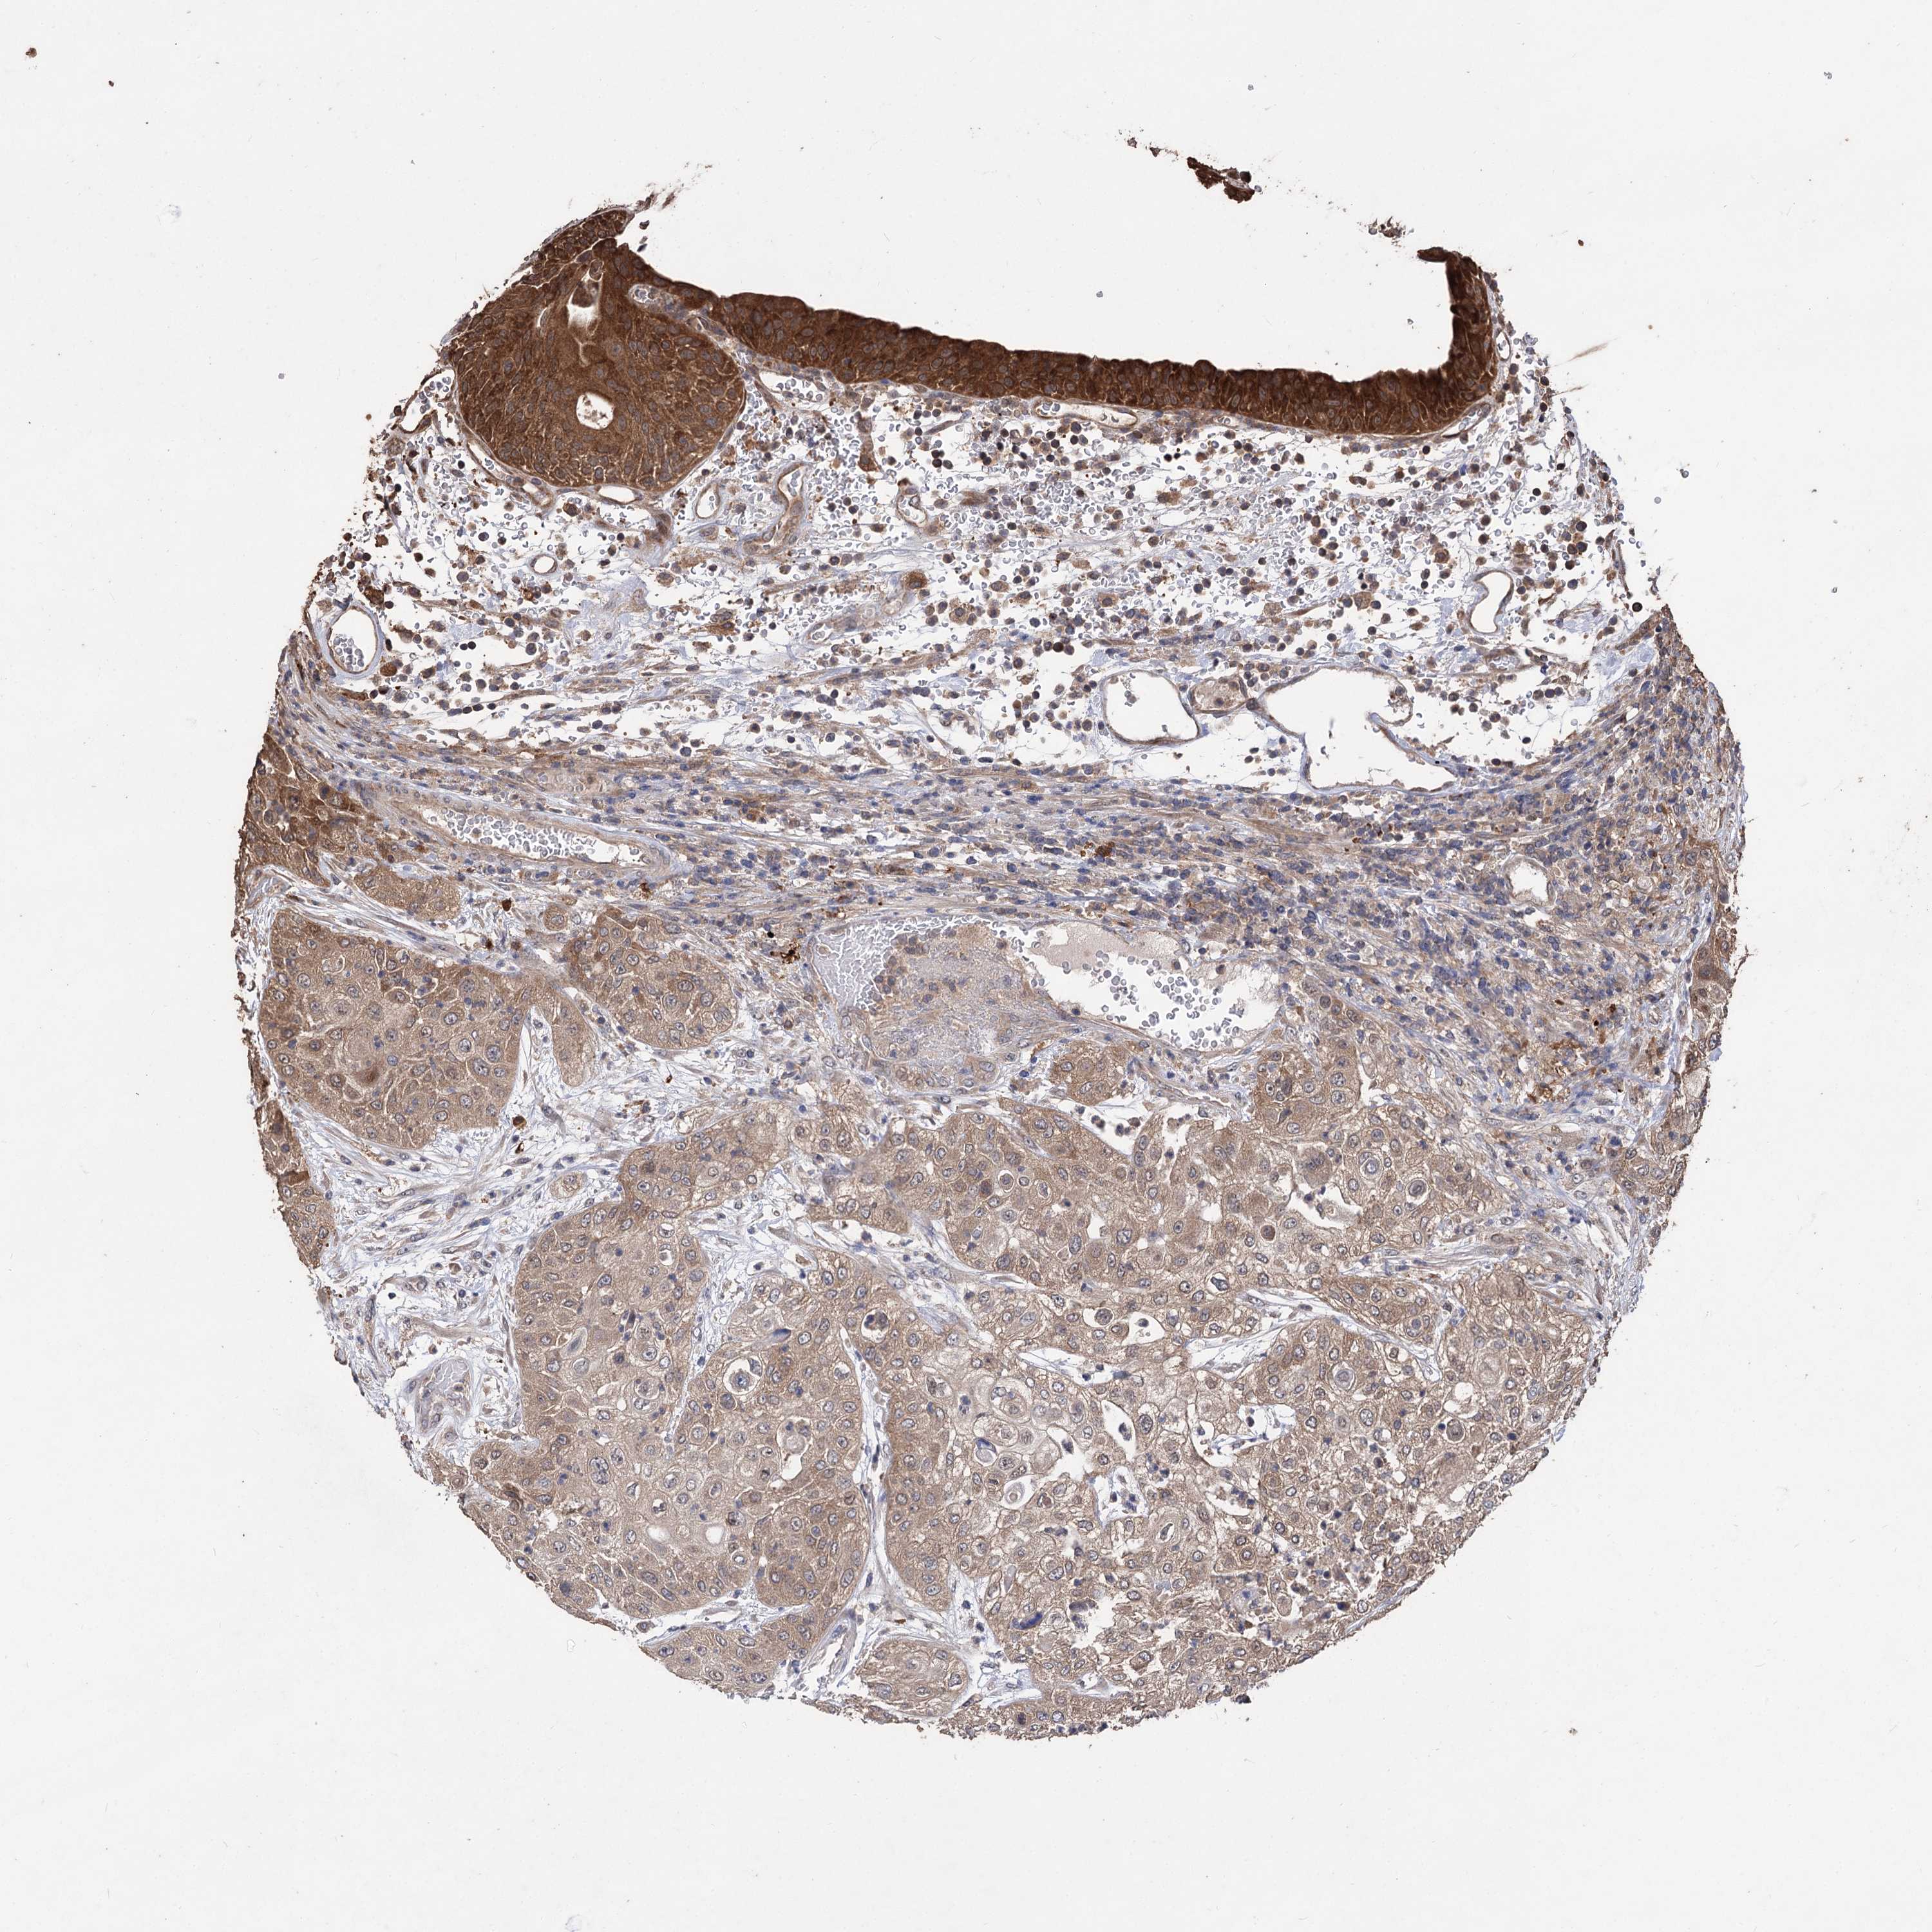

UROTHELIAL CANCER - Protein expressioni

A mouse-over function shows sample information and annotation data. Click on an image to view it in a full screen mode. Samples can be filtered based on level of antibody staining by selecting one or several of the following categories: high, medium, low and not detected. The assay and annotation is described here.

Note that samples used for immunohistochemistry by the Human Protein Atlas do not correspond to samples in the TCGA dataset.

Antibody stainingi

Antibody staining in the annotated cell types in the current human tissue is reported as not detected, low, medium, or high, based on conventional immunohistochemistry profiling in selected tissues. This score is based on the combination of the staining intensity and fraction of stained cells.

Each image is clickable and will lead to virtual microscopy that enables deeper exploration of all samples and also displays staining intensity scores, fraction scores and subcellular localization as well as patient and tissue information for each sample.

Antibody HPA038469

Antibody CAB022664

Antibody CAB034035

Staining

High

Medium

Low

Not detected

Intensity

Strong

Moderate

Weak

Negative

Quantity

>75%

75%-25%

<25%

None

Location

Nuclear

Cytoplasmic/membranous

Cytoplasmic/membranous,nuclear

Urothelial carcinoma, High grade

Urothelial carcinoma, Low grade